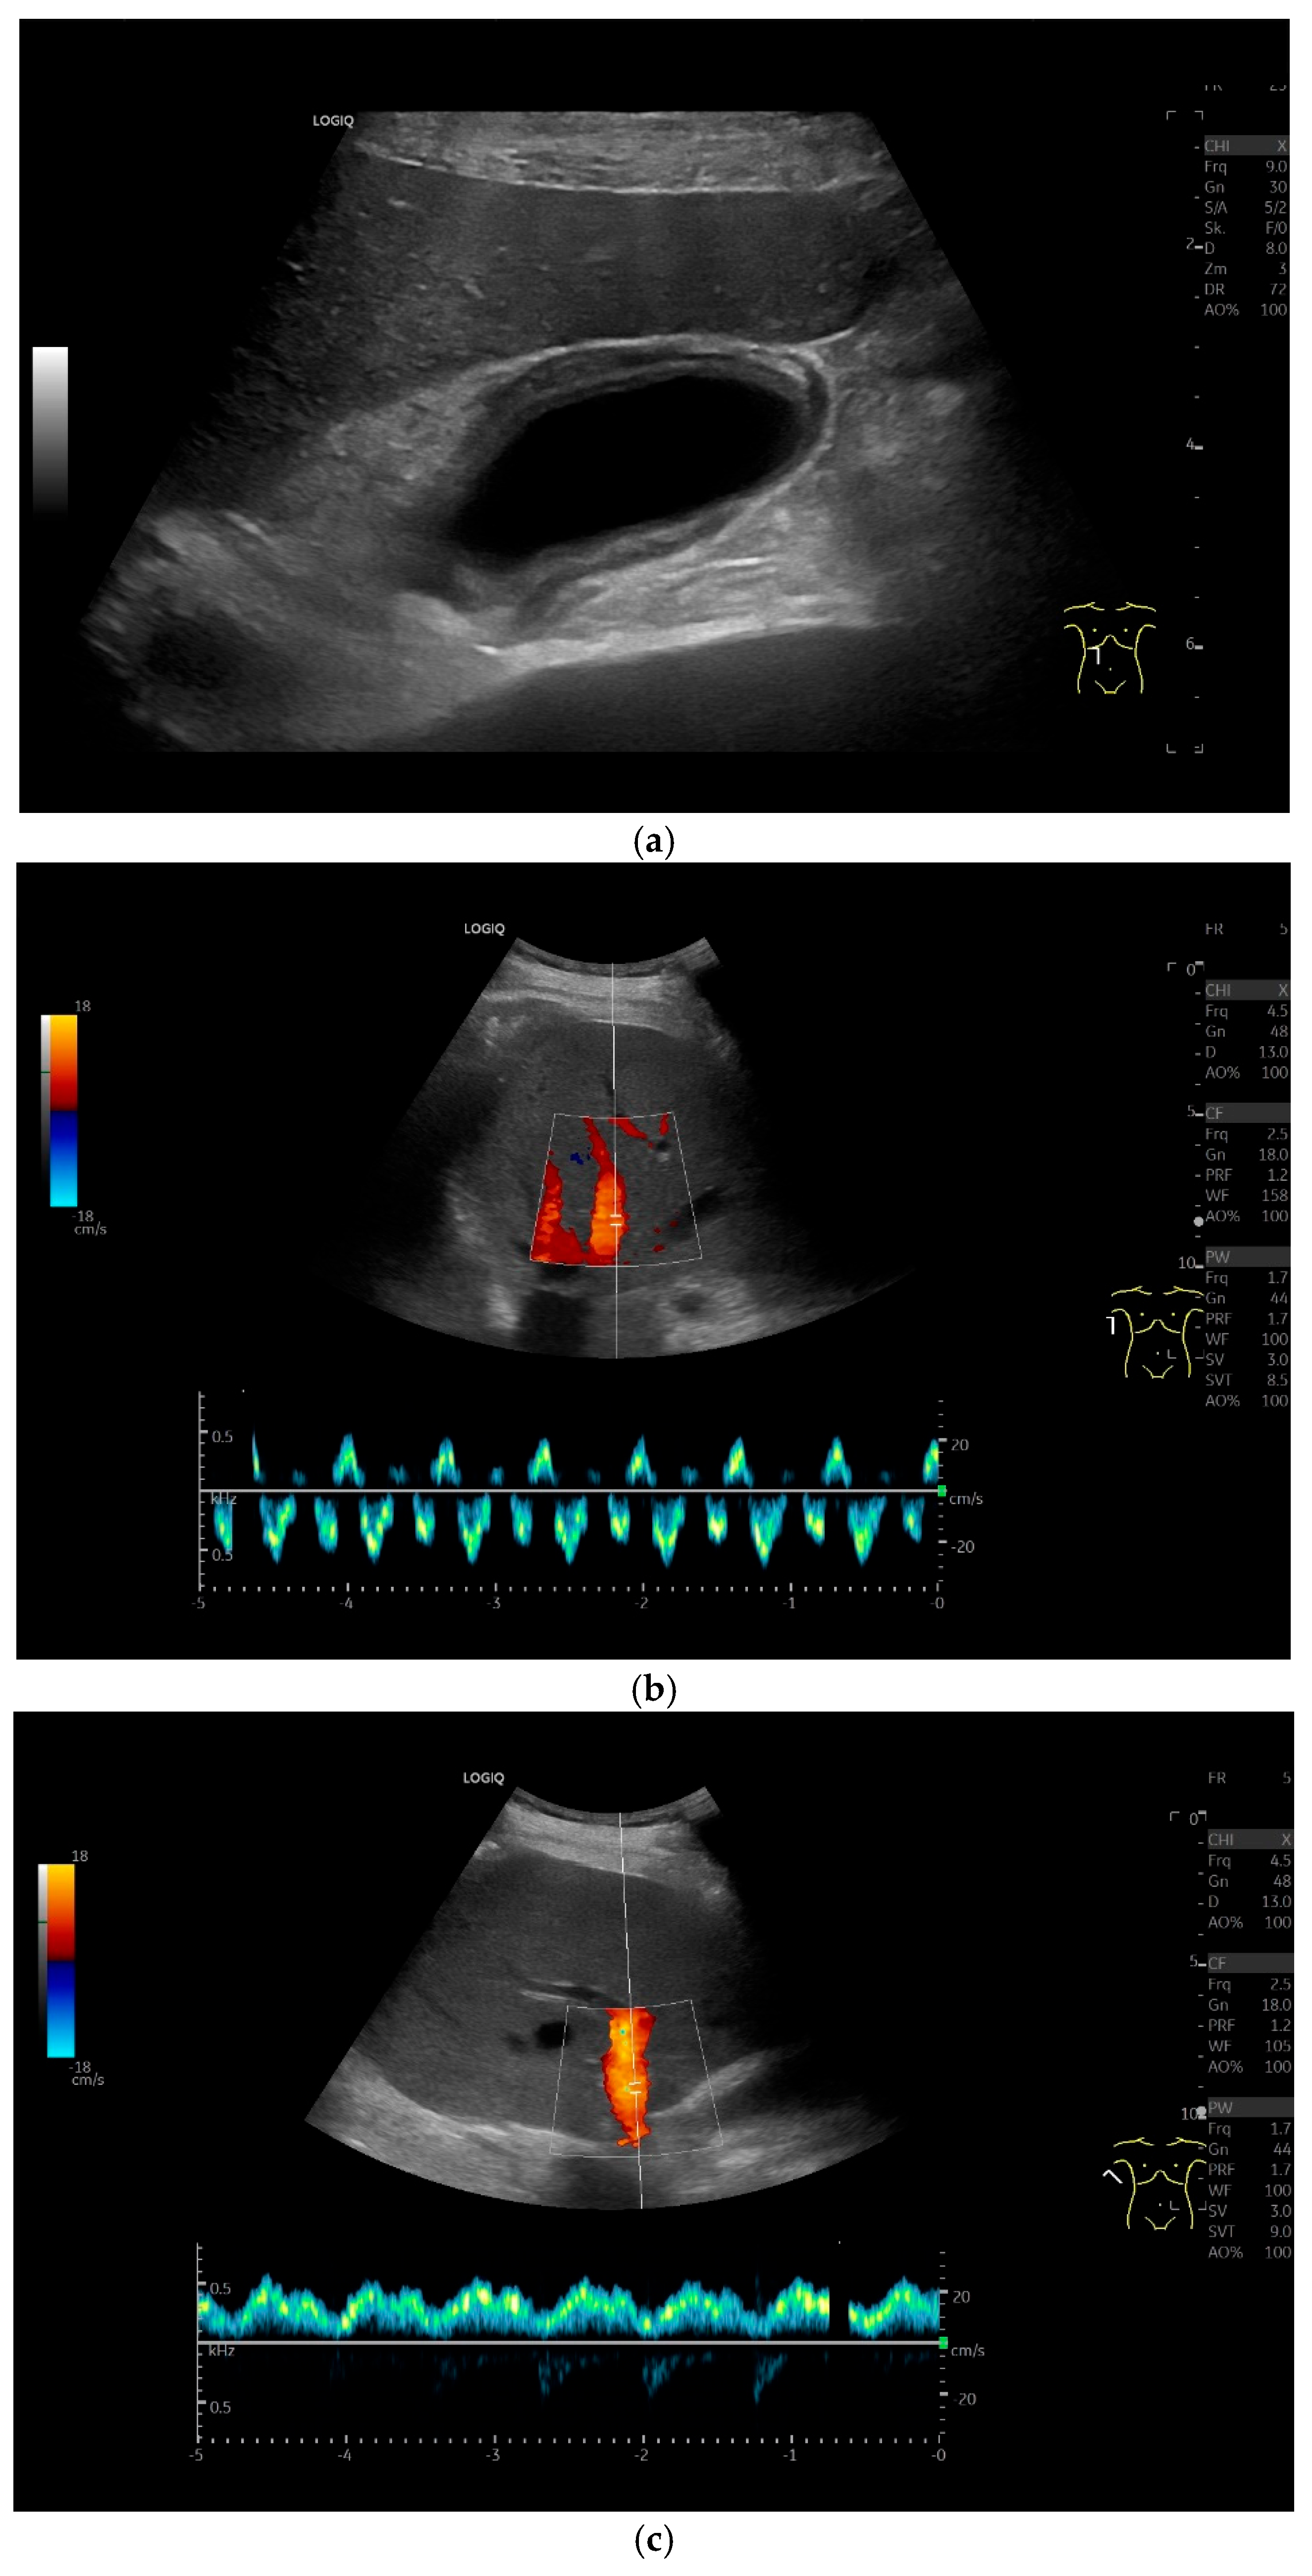

4.5. Gallbladder Hydrops